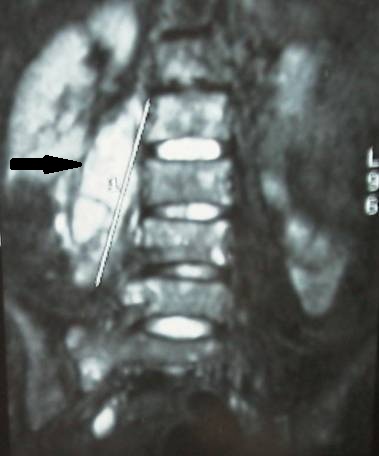

- Figura No 3a

- Figura No 3b

- Figura No 3c

- Figura No 3d

- Figura No 3e

- Figura No 3f

- Figura No 3g

- Figura No 3h

- Figura No 3i

- Figura 3 Texto